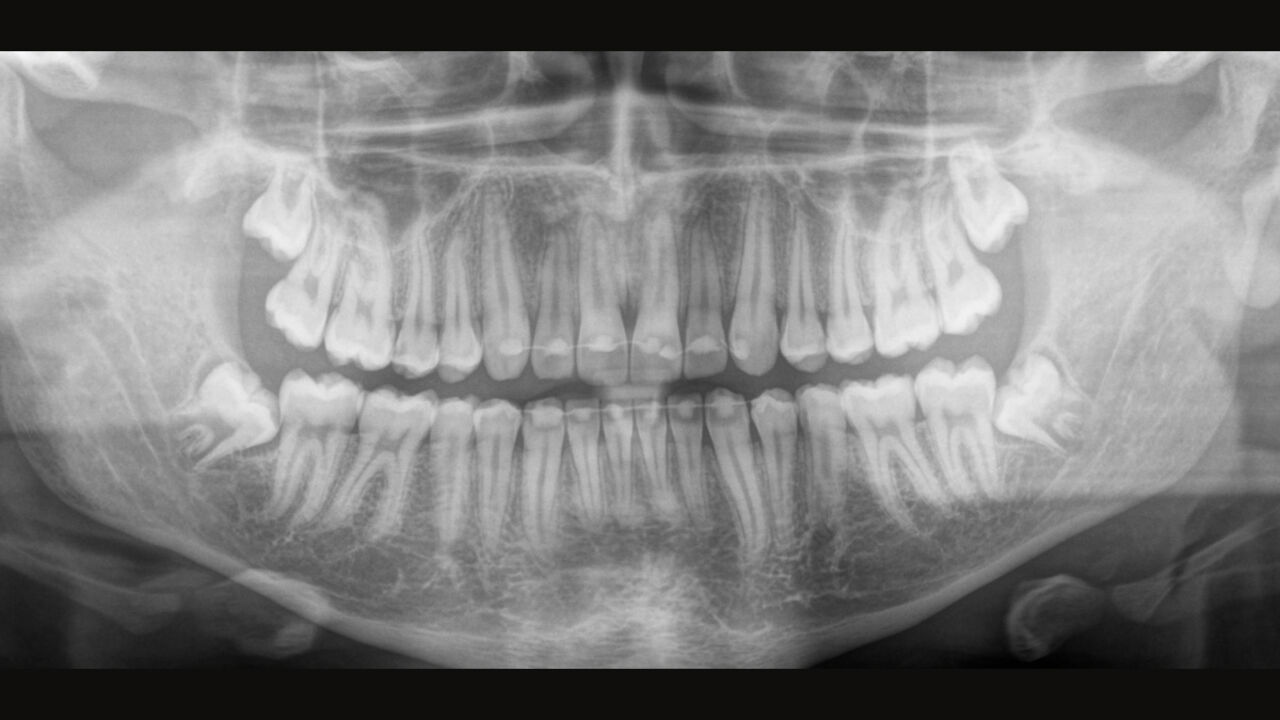

El enfoque correcto es crucial para excelentes radiografías panorámicas. Con la función de autofoco, usted recibirá automáticamente una imagen con la mejor nitidez posible en foco. Los dispositivos de radiología de Dentsply Sirona toman varios miles de imágenes individuales en un ciclo e identifican automáticamente las áreas donde la mandíbula está posicionada de manera óptima. Luego, sin ningún paso manual adicional, estas imágenes se muestran en una nítida imagen final.

Solo algunas partes de la imagen están en foco, mientras que otras áreas están borrosas.

El sistema detecta las áreas relevantes a partir de varios miles de imágenes individuales en un ciclo e identifica automáticamente las áreas donde la mandíbula está posicionada de manera óptima.

Imágenes nítidas.